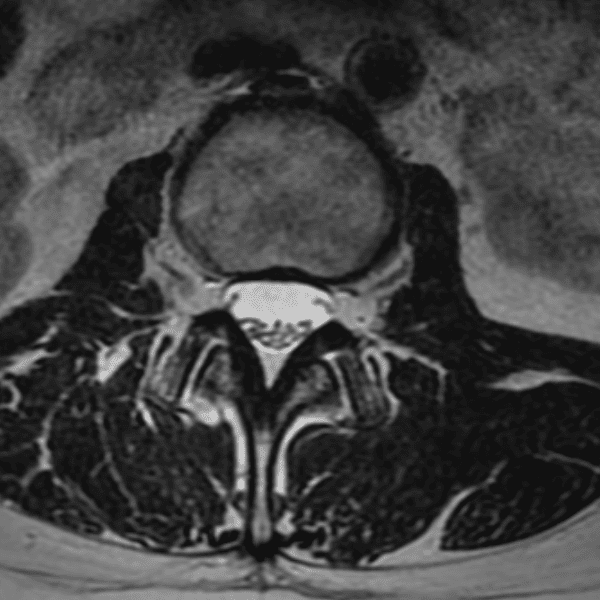

Simulates call by including subtle or difficult cases and some normals.

35 cases